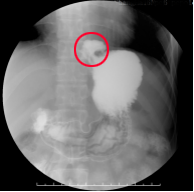

上消化道钡餐可动态见到胃食管反流表现